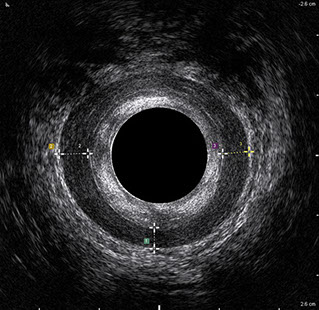

L’ecografia transanale è un esame diagnostico per immagini che consiste nell’introduzione di un trasduttore ad ultrasuoni. Le immagini qualitativamente migliori del canale anale sono ottenute usando un trasduttore rotante, montato in un manipolo rigido, che fornisce un’immagine a 360°. Con le apparecchiature più moderne è anche possibile ottenere immagini tridimensionali.

L’ecografia transanale permette di distinguere la sottomucosa che riveste il canale anale, lo sfintere anale interno, e lo sfintere anale esterno.